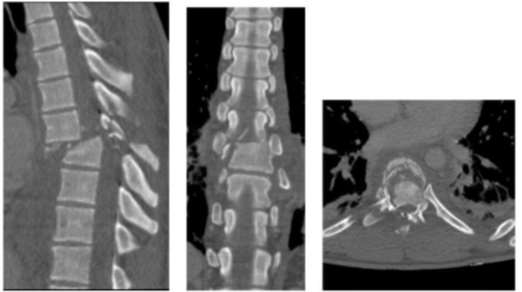

Paciente, sexo masculino, 18 anos, procedente de Jupi-PE, é trazido pelo SAMU com história de queda de motocicleta, sem uso de capacete e após libação alcoólica há 06h. Chega em Unidade de Trauma, em prancha rígida e fazendo uso de colar cervical. Após aplicação do XABCDE e estabilização clínica pelo cirurgião geral plantonista, o neurocirurgião é chamado para avaliação. Paciente apresentava hálito alcoólico, desorientado, pontuando 14 pela ECG (Resposta Ocular = 4 + Resposta Verbal = 4 + Resposta Motora = 6), isocórico, com reflexo fotomotor (RFM) presente bilateralmente, paraplegia e com sondagem vesical de demora (SVD).

Foram realizadas TCs, sendo a de crânio normal e a de toda a coluna com os seguintes achados anormais:

Qual classificação de American Spinal Injury Association (ASIA), pontuação do Thoracolumbar Injury Classification System (TLICS) e tratamento mais adequados para o caso acima, respectivamente?

Caso clínico 2 para as questões 25 e 26.

Qual melhor classificação pode-se dar para as lesões acima, conforme a AOSpine Thoracolumbar Spine Injury Classification System (AOSpineTLSICS)?